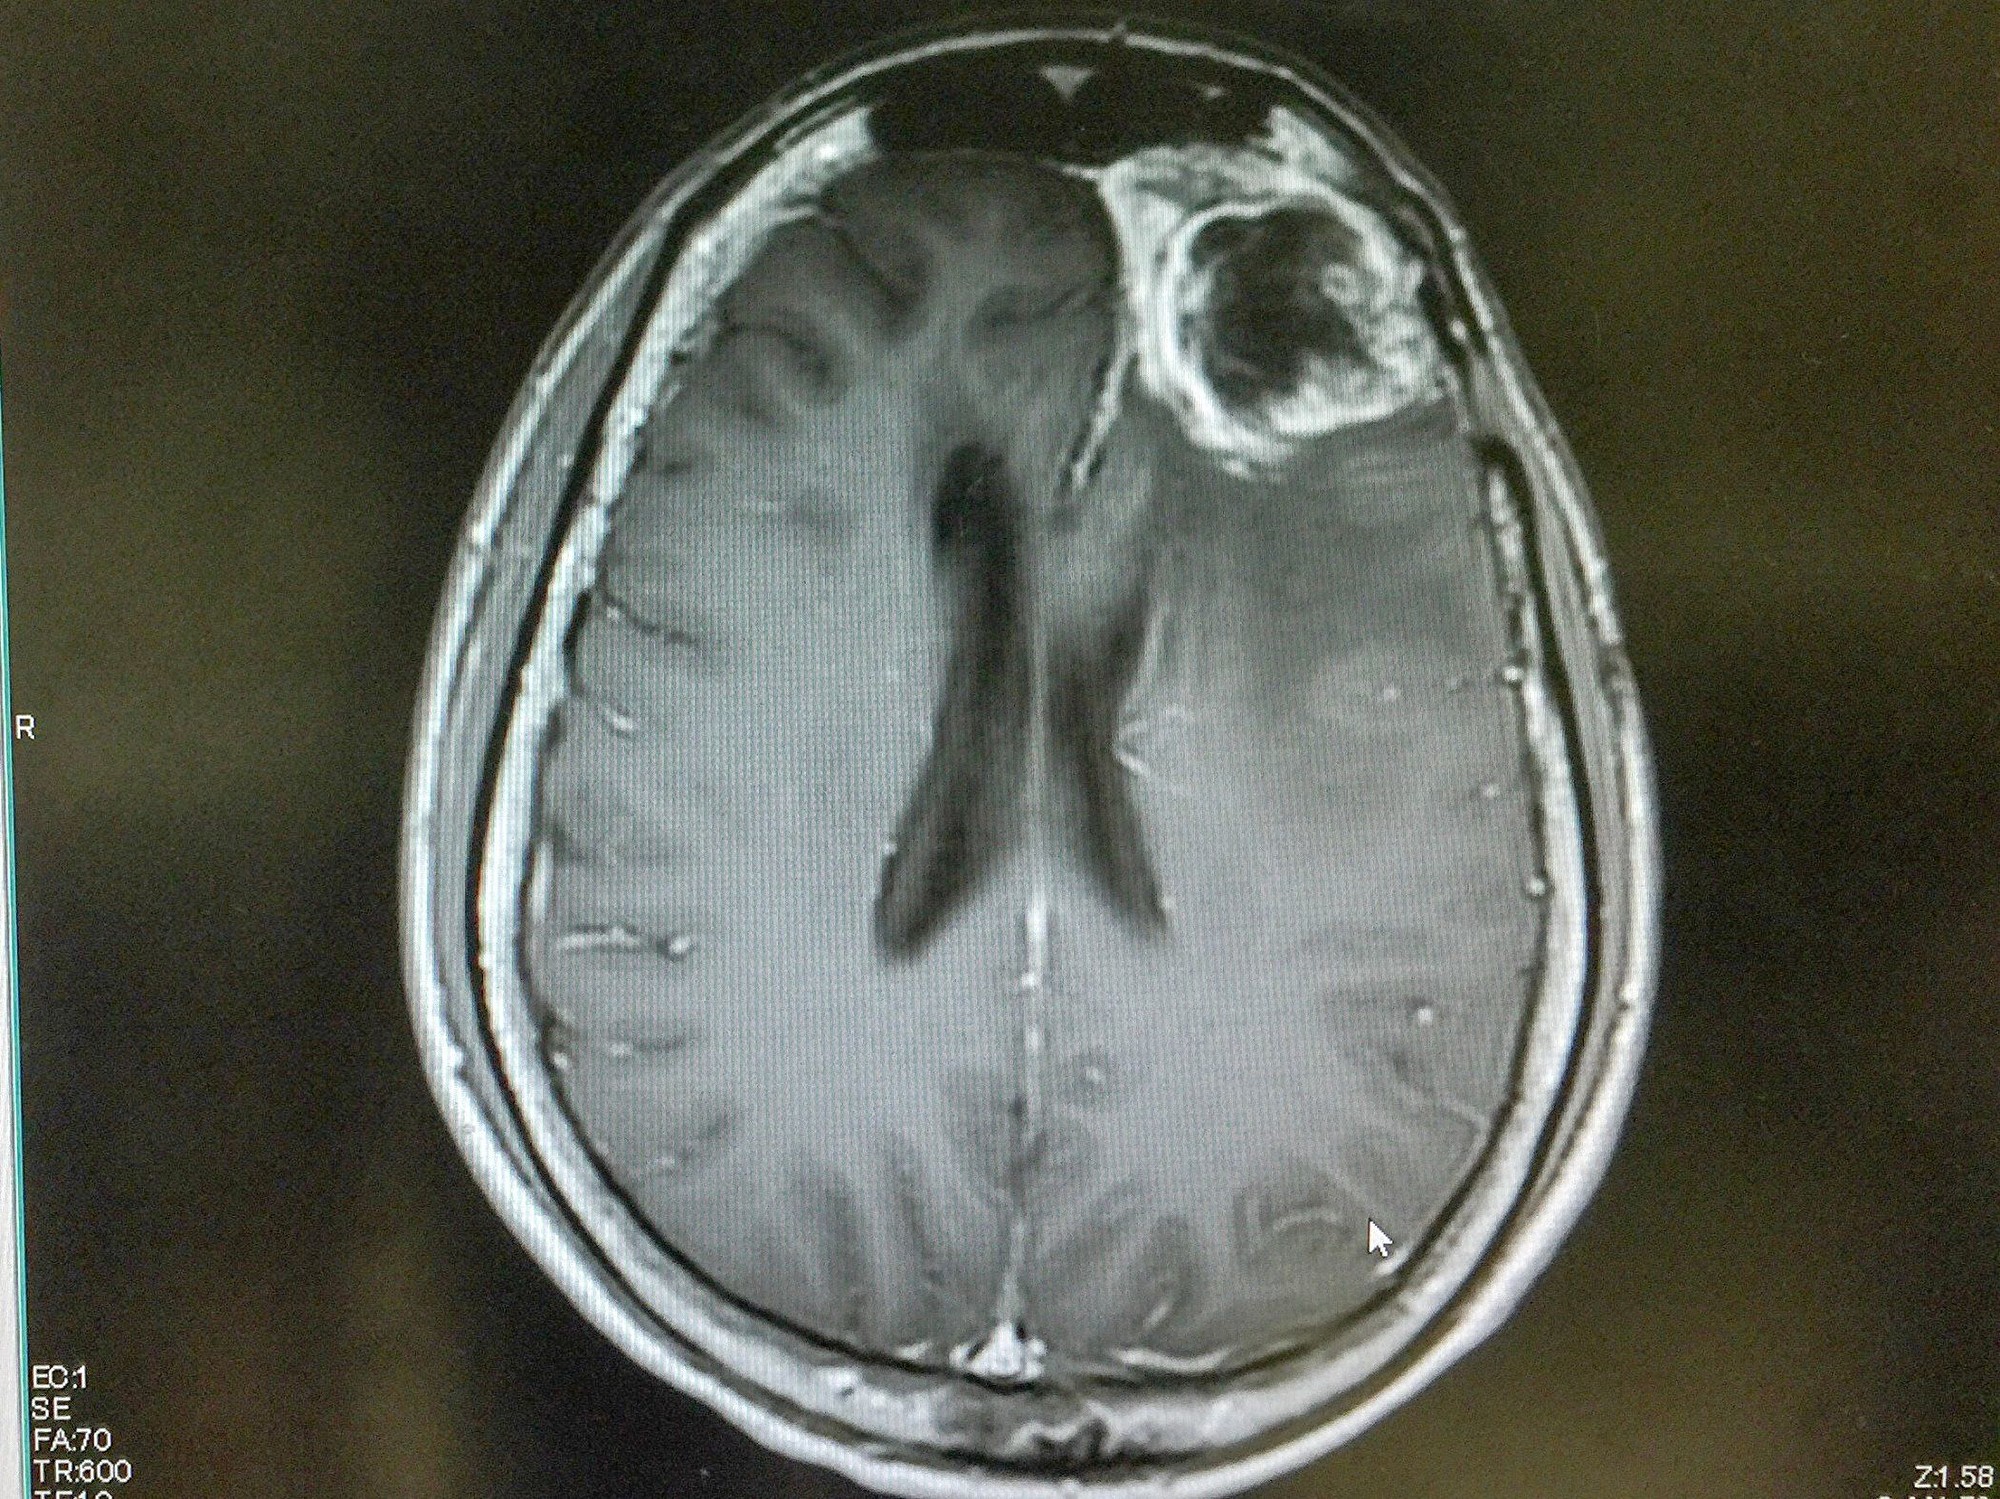

【大纪元2019年12月21日讯】(大纪元记者李少维编译)胶母细胞瘤(glioblastoma)是一种最严重的脑癌,目前基本没有治疗办法。美国一组研究者发明了一种利用超声波突破血脑屏障向脑肿瘤递送药物的方法,在小鼠实验中证明相当有效,已申请临床实验。

主要研究者索纳本德(Adam Sonabend)说:“对于胶母细胞瘤目前基本没有治疗方案。”该研究组已向美国食品药物管理局(FDA)递交了临床实验申请。